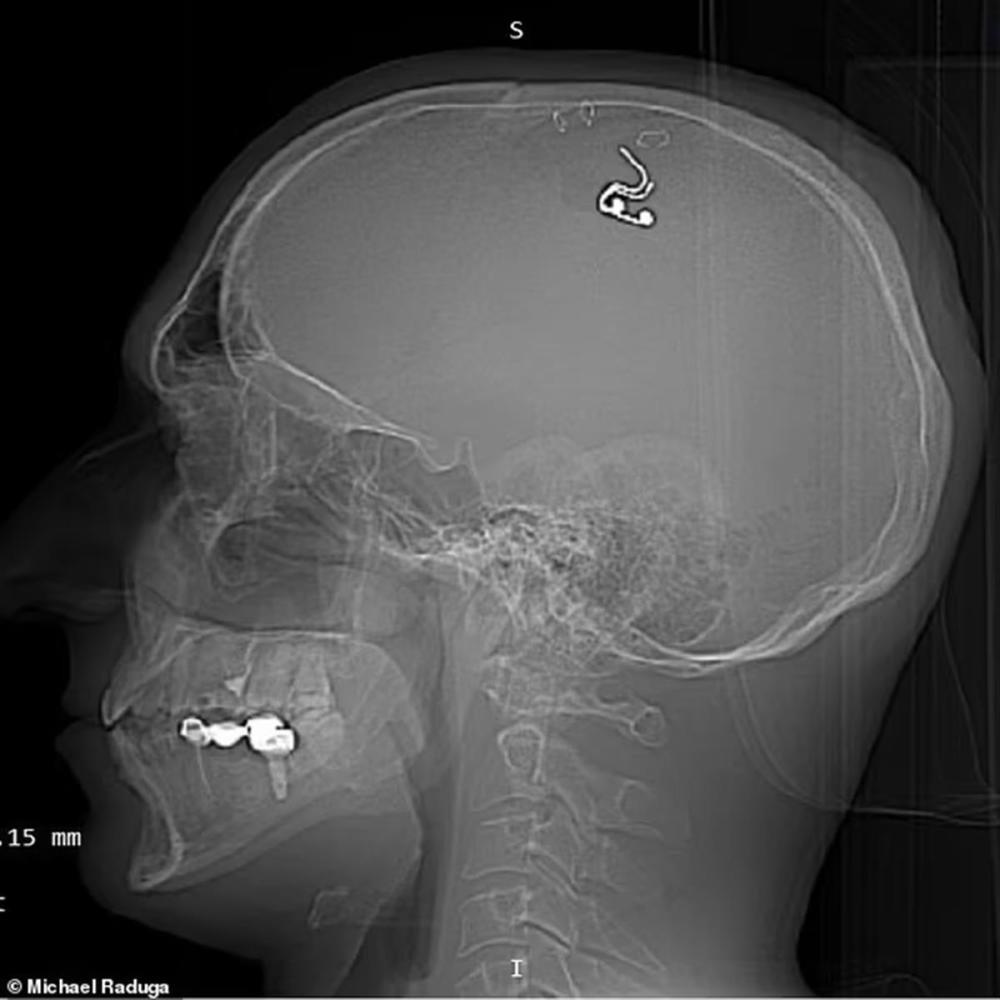

迈克尔·拉杜加大脑中的芯片(图源:每日邮报)

在手术视频中,拉杜加用回形针夹住他的头皮,并用钻头在头骨后部钻孔,随后把一个铂硅植入物植入自己的大脑。整个手术过程中,拉杜加都没有任何专业的神经外科医生指导。由于完全缺乏手术经验,在4个小时的手术中,拉杜加失血近一升,感觉自己几乎要死了。

拉杜加声称,植入物可以帮助他用电来触发梦中的某些动作。然而,手术五周后,拉杜加还是去医院取出了这一植入物。尽管如此,拉杜加仍认为自己进行的这项实验可以帮助人们控制自己的梦境,还将其比作现实版《盗梦空间》。